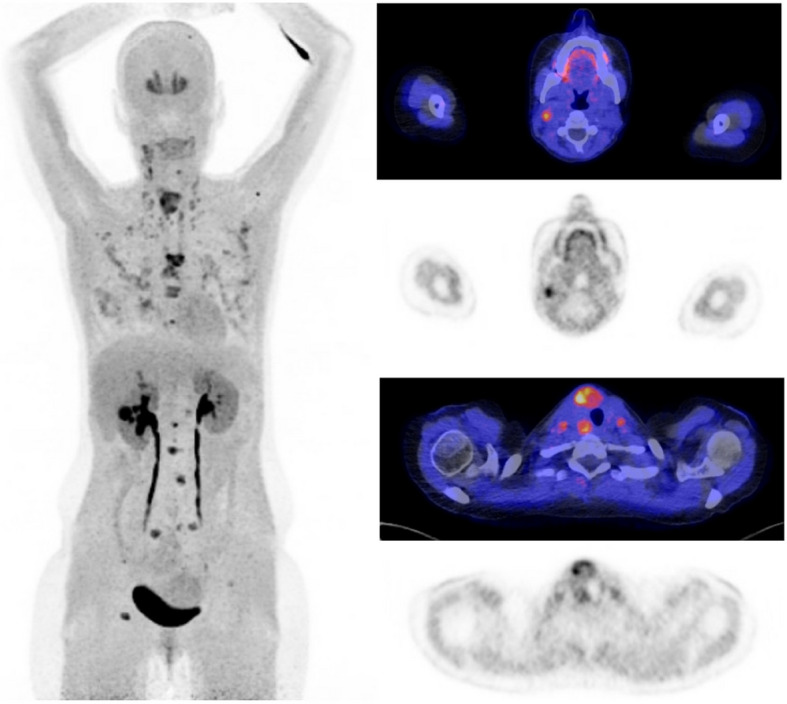

Results: A total of 175 MTC patients were included (91 females and 57 hereditary MTCs). Median age at presentation was 52 years (IQR 38 - 62). Initial treatment included a total thyroidectomy, CND and LND in 155 (89%), 140 (80%) and 59 (33%) patients. Preoperative imaging of the neck included ultrasound (91, 52%), MRI (33, 19%) and CT (31, 18%). PET/CT imaging was performed in 56 (32%) patients (35 18F-FDG PET/CTs and 33 18F-DOPA PET/CTs). Sensitivity for LNM in the central compartment was 72%, 39%, 6%, 42% and 93% for 18F-FDG PET/CT, 18F-DOPA PET/CT, ultrasound, MRI and CT, respectively. Respective specificity rates were 80%, 100%, 100%, 71% and 100%. Sensitivity rates for lateral neck LNM were 89%, 81%, 77%, 76% and 75%, for 18F-FDG PET/CT, 18F-DOPA PET/CT, ultrasound, MRI and CT, while specificity rates were 100%, 100%, 75%, 78% and 50%, respectively. Twenty-three patients had distant metastases on imaging. In total, 14 18F-FDG PET/CTs and 9 18F-DOPA PET/CTs were made in these 23 patients (both in six patients). All but one PET/CT showed distant metastases.

Conclusions: PET/CT is a powerful tool to detect locoregional LNM and can particularly help identify cases where LNDs are required, avoiding reoperation later on. For accurate staging of the central neck, PET may be combined with diagnostic CT. Finally, PET/CT's ability to detect distant metastases may support de-escalation of a surgical intervention when cure is unlikely.